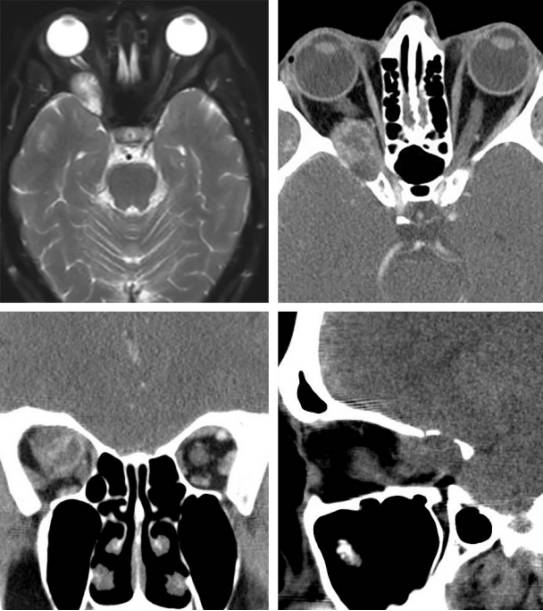

图5. 通过改良OZ入路切除位于眶后上部并导致渐进性视力下降的神经鞘瘤。肿瘤恰好位于红色箭头所示的眶上裂内侧,随后切开眶筋膜将其分离、取出。